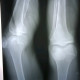

Alo dokter izin diskusi apakah ada fraktur pada pemeriksaan radiologis foto ini? Sepengetahuan saya tidak dok, namun kali masih edema dan tidak bisa digerakkan.

Terimakasih TS 🙏